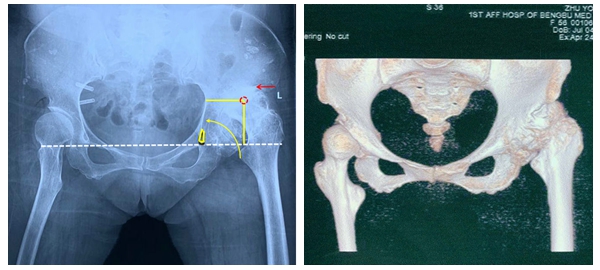

周建生教授接診后第一時間詳細詢問病史、體格檢查(圖一),結合患者術前骨盆平片,髖關節(jié)CT(圖二、圖三)平掃三維重建,診斷為:“左側髖關節(jié)發(fā)育不良(DDH Crowe III型)繼發(fā)終末期骨關節(jié)炎”。向患者建議應用我院自主研發(fā)的”個性化一體化定制髖臼假體”實現(xiàn)DDH精準全髖關節(jié)置換”的治療方案。